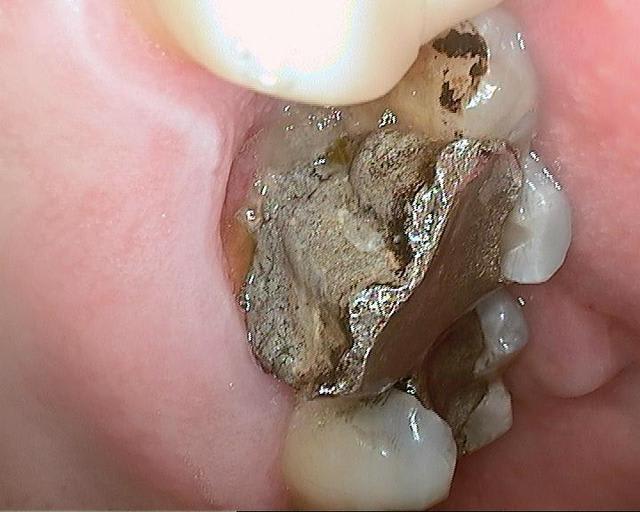

Un patient de 52 ans présente une fracture de racine au site 26.Après division de la racine, extraction de la dent,préparation de la cavité avec un foret conique triangulaire (3 faces,condensation de l´os), puis implantation à 50 Ncm (implant 10mm long, 4,5mm diamètre).Utilisation d´acide hyaluronique pour stimuler la synthèse des ostéoblastes.Pose d´un clip gingival pour préformer la gencive.Après 7 semaines, réalisation d´une empreinte fermée en 5 minutes.Une semaine après, fixation de la couronne définitive ( on observe déjà une ostéointégration).